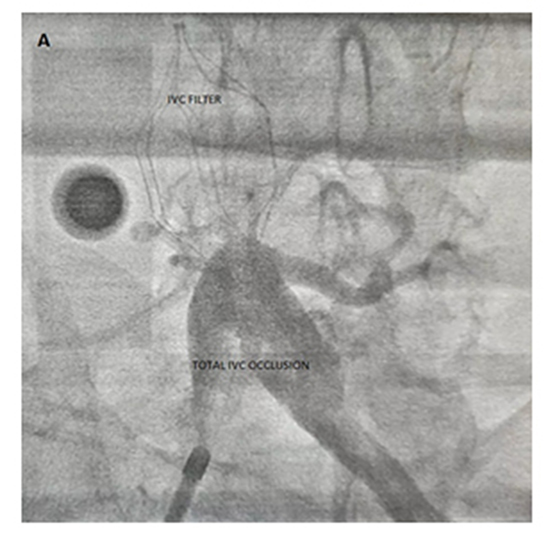

Due to highly symptomatic pharmacological uncontrolled AFib, RFCA was decided in order to achieve long term success in restoring normal sinus rhythm. Transesophageal echocardiography on the day of procedure excluded clot or thrombus. Right femoral vein cannulation was performed, but advancing the guidewire through the IVC was extremely difficult. Peripheral venography revealed complete occlusion of the venous system with no flow through the IVC filter.

Due to highly symptomatic pharmacological uncontrolled AFib, RFA was decided in order to achieve long term success in restoring NSR.TEE on the day of procedure excluded clot or thrombus. Right femoral vein cannulation with modified Seldinger technique was performed, but advancing the guidewire through the IVC was extremely difficult. Peripheral venography revealed complete occlusion of the venous system with no flow through the IVC filter. We discussed the options we had with the patient’s family: transhepatic access, subclavian access or referral for epicardial approach.

Figure 1. Peripheral venography revealed no flow through the IVC filter